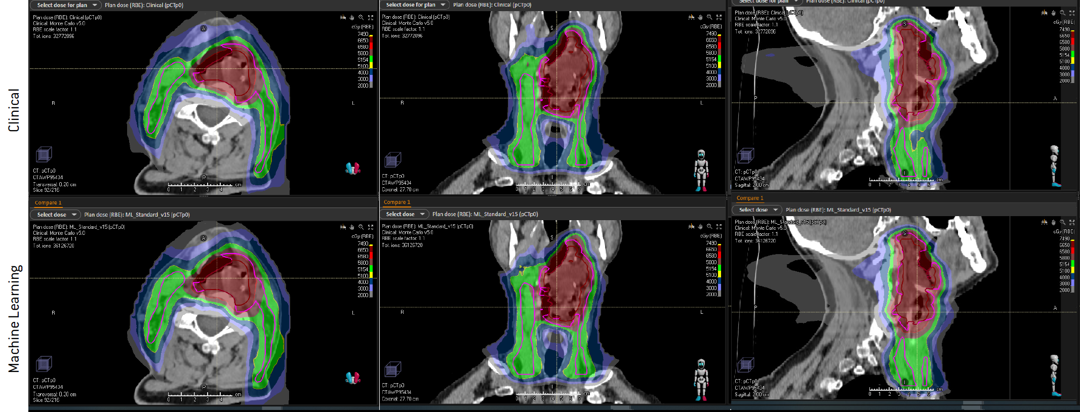

Table 1 shows the resulting toxicity and dose values in comparison between a clinical IMPT plan and the machine learning IMPT plan for a representative patient. Figure 1 shows the dose for the patient, both the robustly mimicked machine learning plan, and the clinical plan. Moreover, Figure 2 depicts the plan-robustness analysis of the clinical and machine learning plans in which DVH curves are shown for a large number of setup- and density-error scenarios. In the evaluation, the isotropic position, and a density uncertainty, were analogous to that of the clinical plans used for training of the machine learning algorithm. Both spatial dose visualization and DVH comparison for scenarios demonstrate that the machine learning generated IMPT plan is of clinical quality.